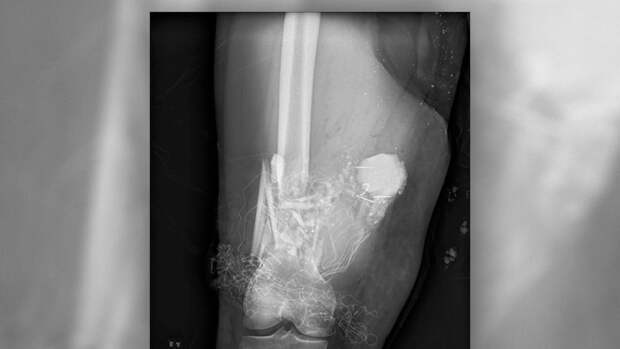

Атлет получил тяжелые травмы на чемпионате Евразии. Во время приседа Радашкевич не смог справиться со штангой весом 250 кг. Его доставили в больницу с переломом голени, а также с закрытым перелом двух берцовых костей на ноге.